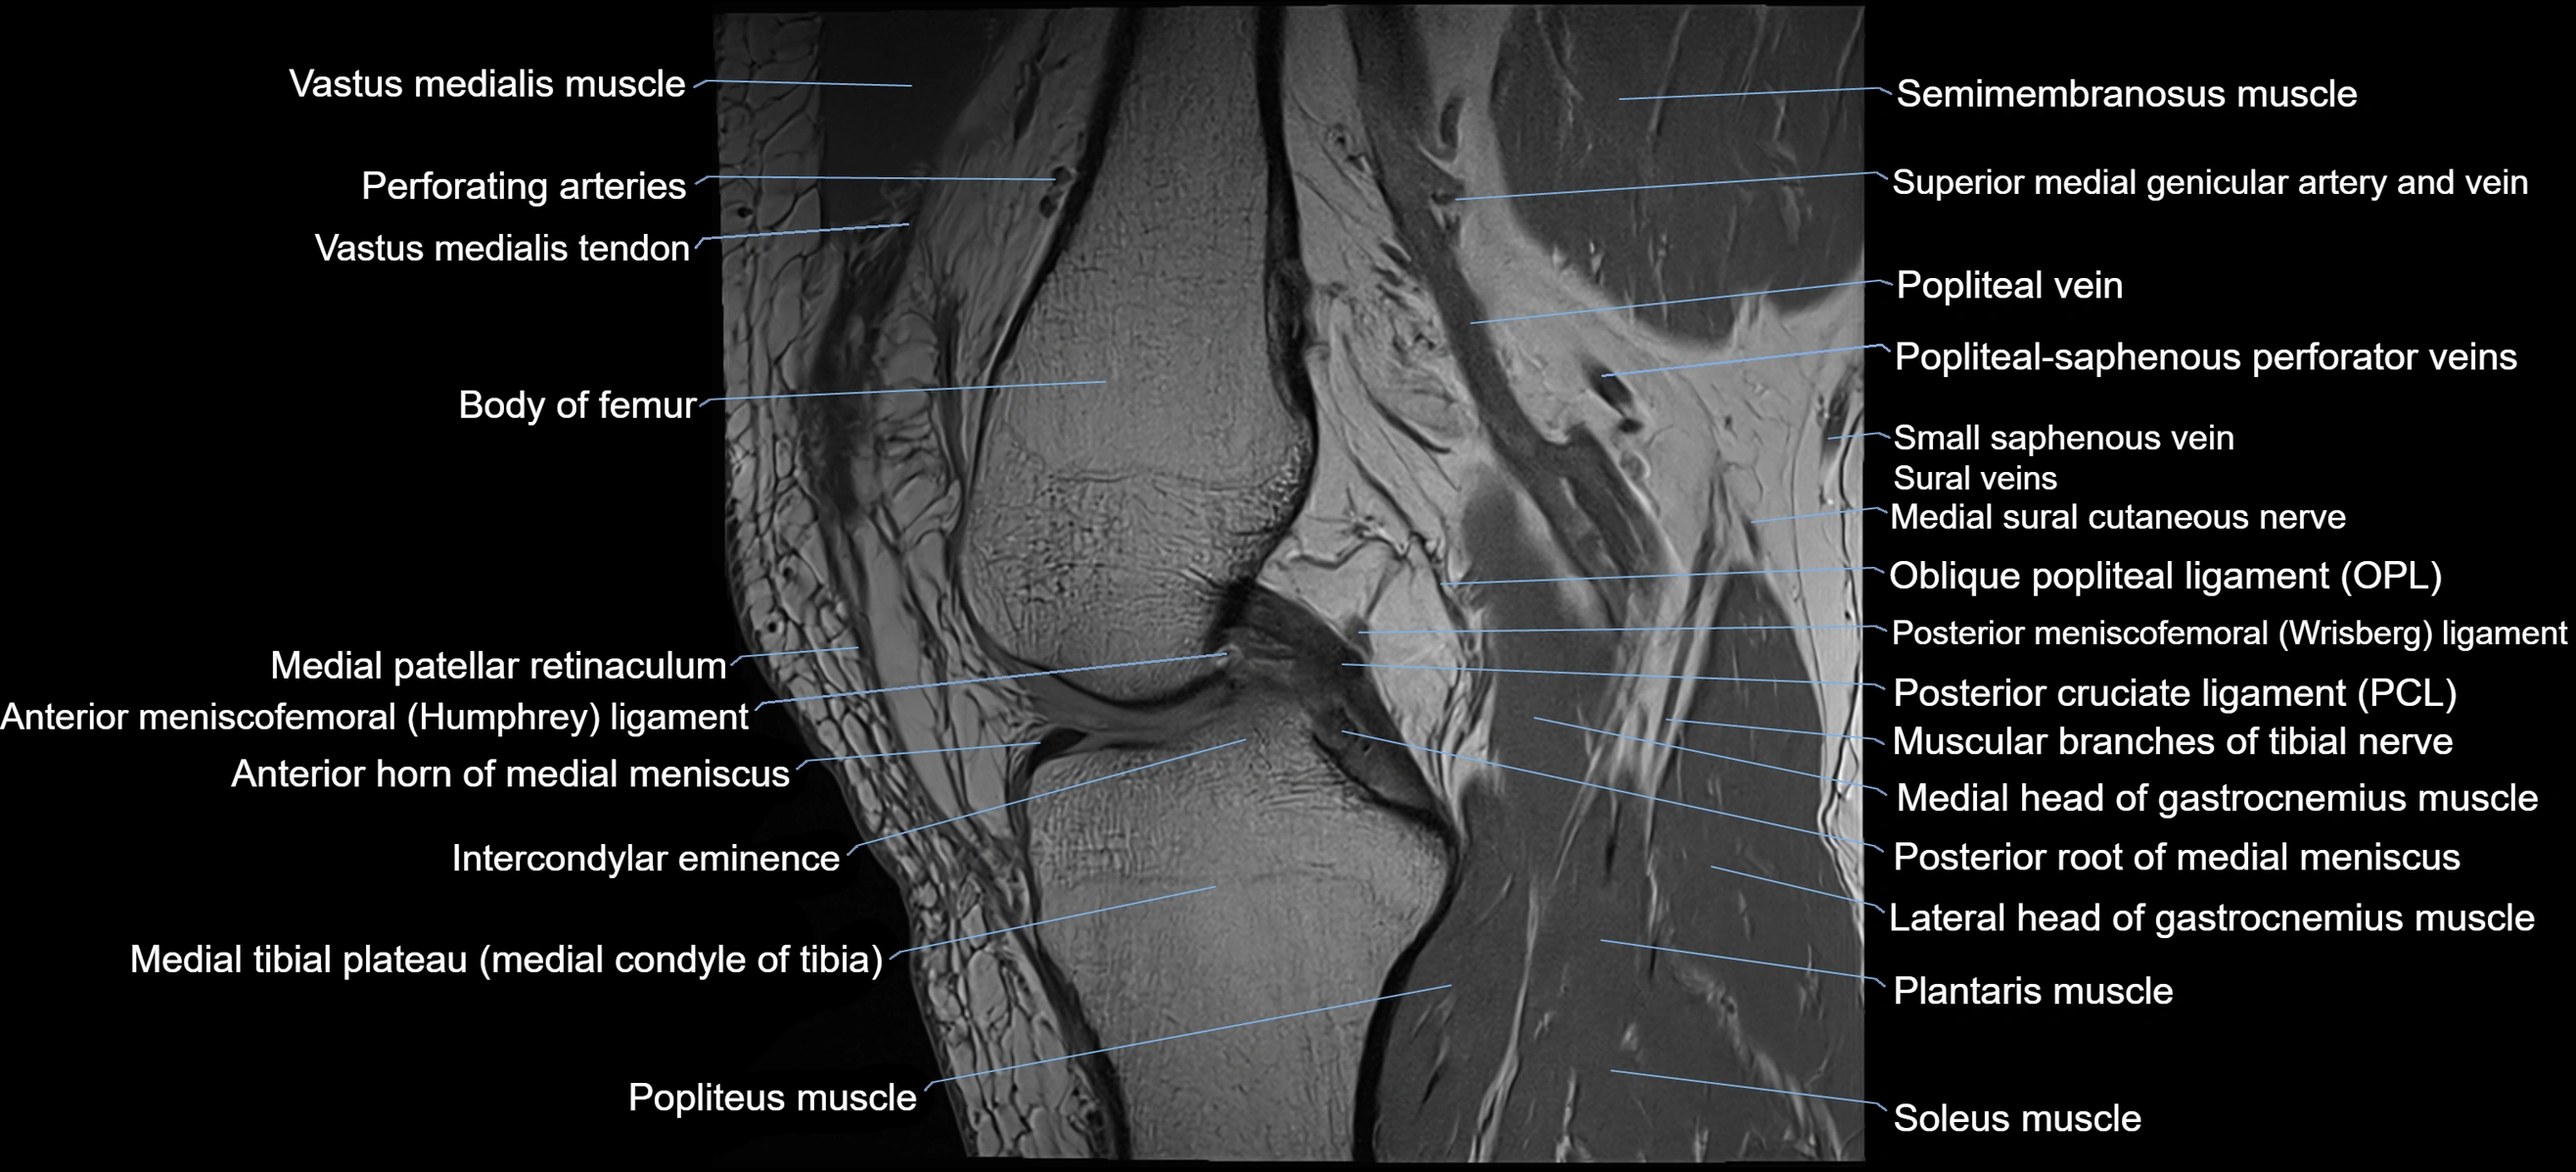

- Oblique popliteal ligament

- Posterior cruciate ligament

- Posterior meniscofemoral ligament

- Posterior root of medial meniscus